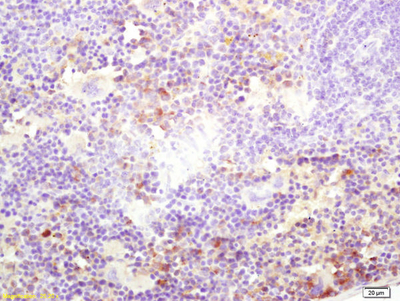

KINESIN Antibody^ KINESIN Polyclonal Antibody, Host: Rabbit, Species: Human, Mouse, Rat, Isotype: IgG, Synonymns: KNS; KINH; KNS1; UKHC; HEL-S-61, Application: IHC-P, IF(IHC-P), 100ul